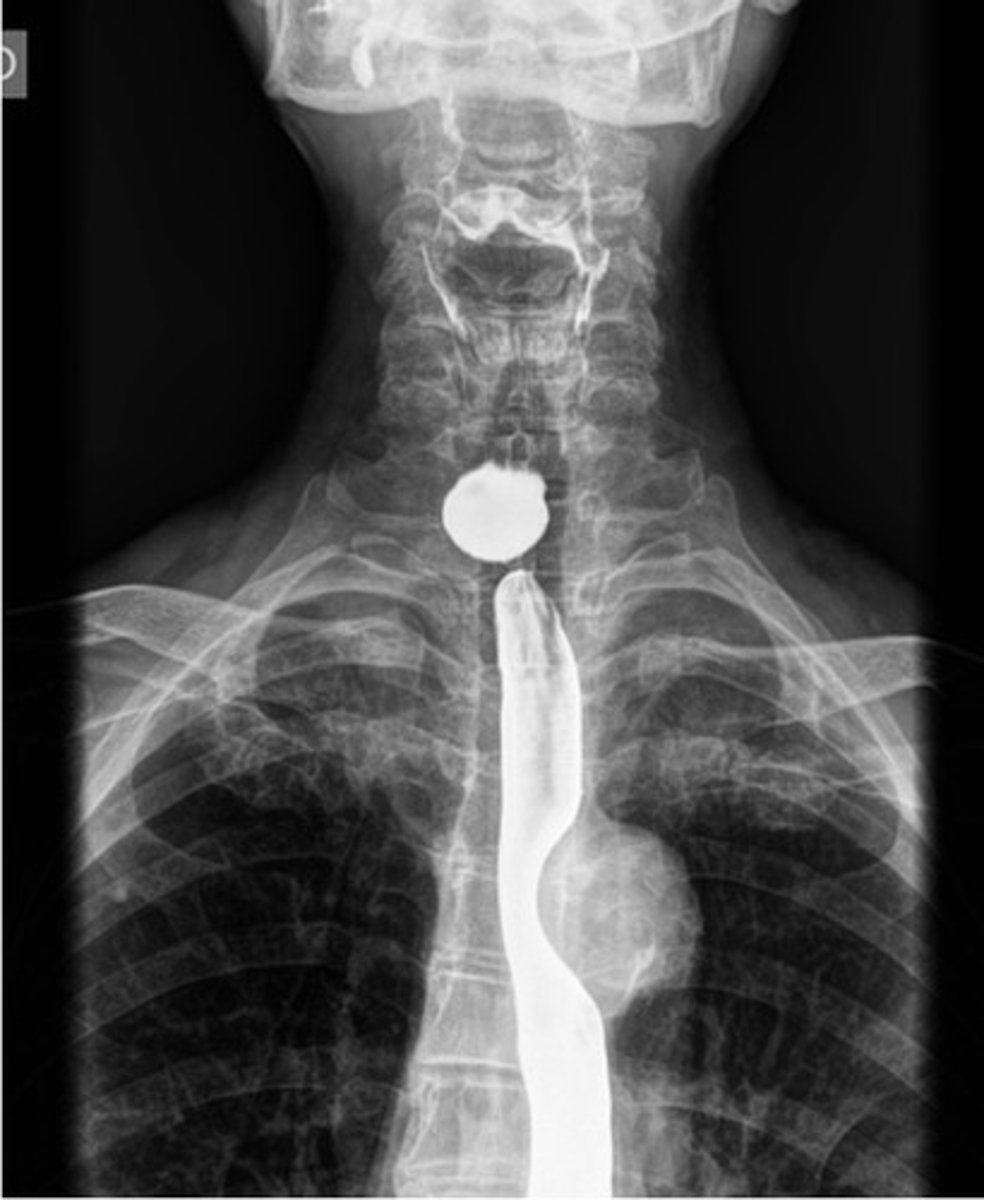

esophagus on barium swallow

cricopharyngeal achalasia/Zenker’s diverticulum

Zenkers diverticulum

Zenkers diverticulum (pic 2)

Zenkers diverticulum (pic 3)